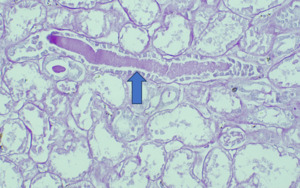

On Light microscopy, The H &E-stained sections of renal biopsy showed features of acute tubular epithelial cell injury with swollen, attenuated lining epithelium. Numerous tubules showed pink to red brown casts in the lumen which were grainy to globular and ropy at places. (Figure 1). The casts appeared weakly PAS positive (Figure 2) and fuchsinophilic on MT stain (Figure 3). On IHC, these casts gave positive staining for myoglobin (Figure 4).

According to one study, other associated finding may be of arterial sclerosis and deposition of calcium oxalate.3 Myoglobin casts are usually appeared eosinophilic to brown granular in H&E stain, are weakly PAS positive and fuchsinophilic in MT stain. Differential diagnosis of Myoglobin casts includes other pigment casts like haemoglobin casts and bile casts.5,11–13

As there are no morphological characteristics to differentiate between them, specific IHC for myoglobin and haemoglobin are required as they do not cross react with any other casts. Bile casts are yellow-brown, stain positive (dark green) with Hall stain and usually occurs when serum bilirubin is very high (>20 mg/dL).4,13